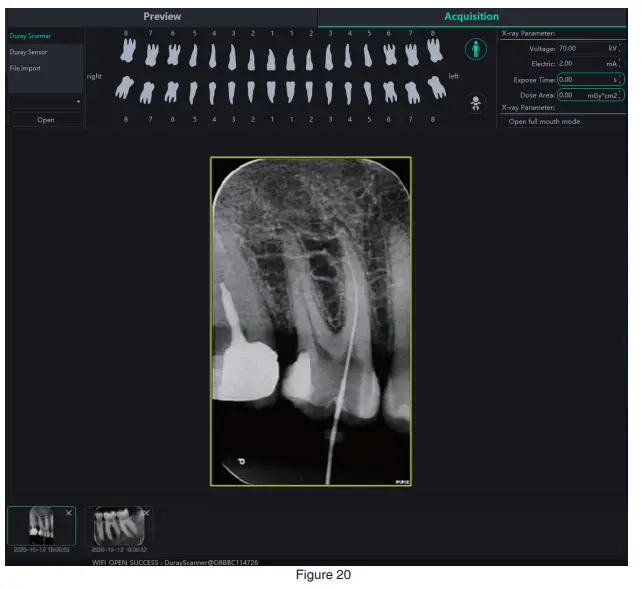

- Image acquisition

After entering the software interface, the WIFI name will be displayed in the software status bar. Click the “Acquisition” button, connect the Duray Scanner DC1 device to WIFI, and select the Duray Scanner DC1 device type. When the device is connected, the IP address will be displayed under the device type. Click “Open”, the device will enter the acquisition state, and start to acquire images. As is shown in Figure 20: